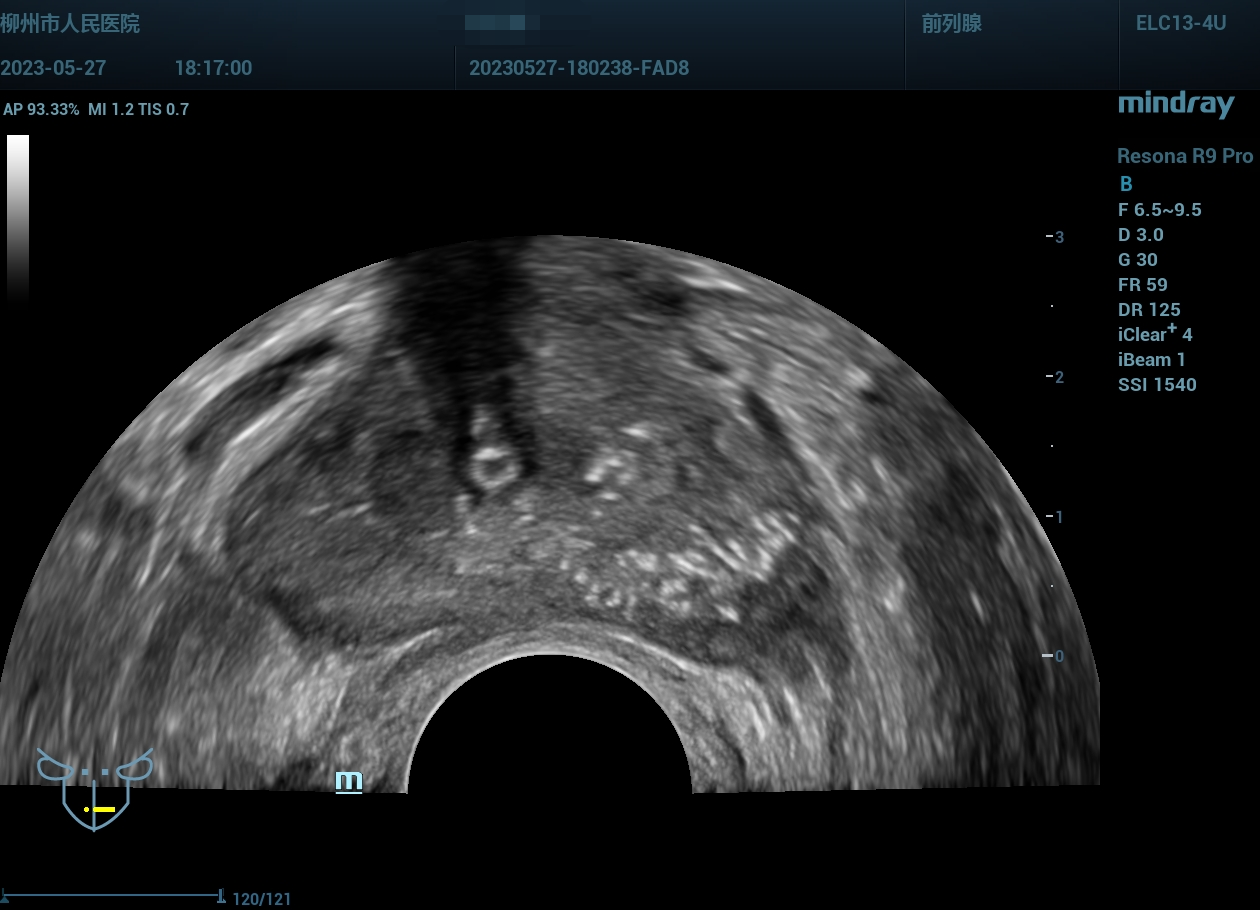

经会阴前列腺穿刺,病例实操(前列腺癌),柳州市人民医院,2023年

老年男性

经会阴前列腺穿刺,病例实操(前列腺癌),柳州市人民医院,2023年-主页丨今日超声